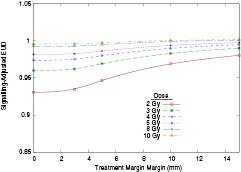

Due to normal tissue toxicities, margins are particularly significant in hypo-fractionated treatments. However, signalling-driven effects are known to saturate at higher doses (Butterworth et al 2011, Butterworth et al 2012), suggesting they may have a reduced importance for larger fractions. Figure 3 presents normalised signalling-adjusted EUDs for varying fraction sizes (i.e. signalling-adjusted EUD divided by the physical plan EUD).

Figure 3. Effects of target diameter and margin on normalised signalling-adjusted EUD, at varying physical doses. (a) Effect of varying target diameter with no margins at different doses. (b) Effect of varying treatment margin on a 20 mm target volume, at different doses.

Download figure:

Standard image High-resolution imageWhile similar trends are seen, the scale of the effect is dramatically reduced at higher doses. For zero margin cases, 4 Gy fractions see roughly half the reduction in cell killing at 2 Gy, with the effect reduced to a few percent at the highest doses. This has the additional effect of reducing the sensitivity to margins. While 10 mm margins increased EUDs for 20 mm targets by roughly 5% at 2 Gy, this is on the order of 1% at 4 Gy.